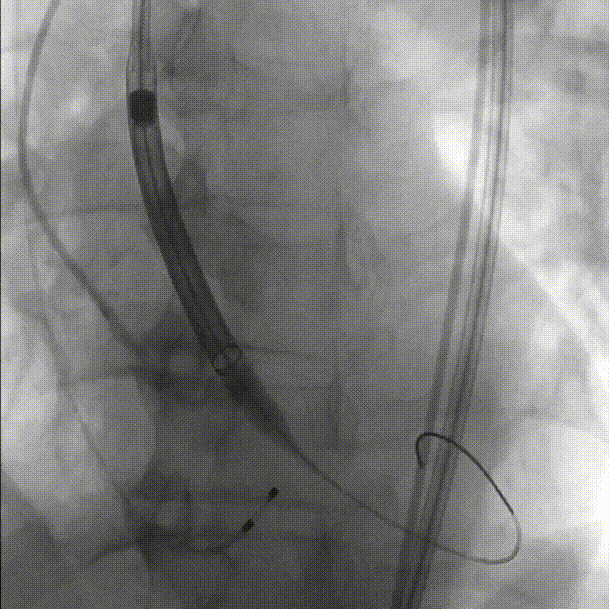

初始定位,左右窦重叠视图开始释放:

释放中期,快速起搏下释放到80%切换视图,并借助食管心超评估深度和反流情况:

完全释放和瓣膜脱钩: